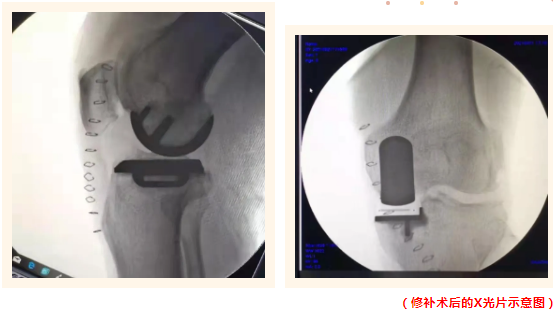

膝關(guān)節(jié)修補(bǔ)術(shù)(單髁置換)屬于保膝范疇,是一種精準(zhǔn)治療膝關(guān)節(jié)單間室磨損的微創(chuàng)新方法,類似于補(bǔ)牙的原理,把磨損的部位巧妙地以特殊材料修補(bǔ)起來,保留了沒有磨損的自然部分軟骨,完全保留了對(duì)膝關(guān)節(jié)穩(wěn)定起到重要作用的所有的韌帶系統(tǒng)。

誠(chéng)德骨科醫(yī)院集團(tuán)已廣泛成熟開展膝關(guān)節(jié)單髁置換手術(shù)這項(xiàng)有著優(yōu)異效果的醫(yī)學(xué)技術(shù)。與全膝關(guān)節(jié)置換術(shù)比較,單髁置換手術(shù)時(shí)間短、創(chuàng)傷小、出血少、保留自身骨量和韌帶、術(shù)后病人感受好,功能恢復(fù)快,關(guān)節(jié)活動(dòng)不受限制,手術(shù)并發(fā)癥少,牛津活動(dòng)平臺(tái)單髁,術(shù)后關(guān)節(jié)功能更接近人體生理狀態(tài),成為了膝關(guān)節(jié)骨性疾病病人的福音。